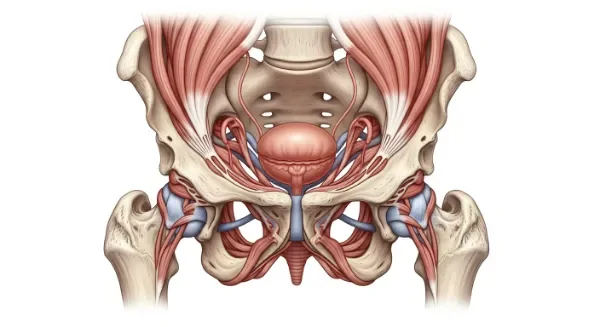

괄약근 약화, 괄약근에 대한 이해 넓히고 적절한 관리가 필수 현대인들은 다양한 건강 문제에 직면하고 있으며, 특히 소화기...

몸속의 신체 기능을 조절하는 괄약근, 괄약근 건강이 삶의 질을 바꾼다 우리 몸은 여러 기관이 정밀하게 조화를 이루며...